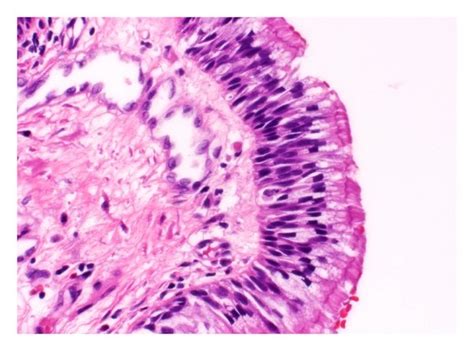

Pseudostratified Ciliated Columnar / / The cells that comprise the epithelial membranes are variously shaped and are named accordingly.. Includes secretory, nonciliated cells (with basal nuclei). Its function is to protect these trachea composes of pseudostratified columnar, ciliated epithelium, goblet cells. Pseudostratified ciliated columnar epithelium consists of a single layer of cells. A pseudostratified columnar epithelium is a tissue formed by a single layer of cells that give the appearance of being made from multiple layers, especially when seen in cross section. Find out information about pseudostratified ciliated columnar epithelium.

Epithelial tissue lines the inner and outer surfaces of organs in the body and function in processes of secretion, absorption. A type of epithelium in which all cells reach to the basement membrane but some extend toward the surface only part way. The pseudostratified columnar epithelium is found in different parts of the body and each specific location serves different functions. The cells that comprise the epithelial membranes are variously shaped and are named accordingly. Ciliated pseudostratified columnar epithelia is found lining the trachea and upper respiratory tract.

Ciliated pseudostratified columnar epithelia is the type of respiratory epithelium found in the linings of the trachea as well as the upper respiratory tract. Pseudostratified ciliated columnar epithelium consists of a single layer of cells. Epithelial tissue lines the inner and outer surfaces of organs in the body and function in processes of secretion, absorption. Learn about pseudostratified ciliated columnar epithelium with free interactive flashcards. Pseudostratified ciliated epithelium lines the nasal cavities, trachea, and bronchi. Posteriorly, the epithelium is a pseudostratified ciliated columnar epithelium that covers the respiratory regions (formed by the maxilloturbinates).45,107,110 the superior turbinate. As it rarely occurs as squamous or cuboidal epithelia. Cliffsnotes states that the pseudostratified characterization comes from the fact that ciliated columnar epithelium cells appear to have multiple layers when there is actually just one cell.

This gives the appearance of multiple layers. Epithelial tissue lines the inner and outer surfaces of organs in the body and function in processes of secretion, absorption. 200 to 300 cilia per cell; Lines the nasal cavities, trachea, and bronchi by secreting mucus by goblet cells and move mucus with cilia. + pseudostratified columnar epithelial tissue. Histology of trachea histology slide of trachea histological slide of trachea. Pseudostratified ciliated columnar epithelium video. A pseudostratified epithelium is a type of epithelium that, though comprising only a single layer of cells, has its cell nuclei positioned in a manner suggestive of stratified epithelia. The cells that comprise the epithelial membranes are variously shaped and are named accordingly. The respiratory airways are lined by a pseudostratified columnar epithelium with a variety of distinct cell types including. As it rarely occurs as squamous or cuboidal epithelia. Crogvpseudostratified columnar tumor cells present. Ciliated pseudostratified columnar epithelia is the type of respiratory epithelium found in the linings of the trachea as well as the upper respiratory tract.

Unlike simple columnar epithelium, the nuclei are arranged at different levels within the cells. Pseudostratified ciliated epithelium lines the nasal cavities, trachea, and bronchi. Histology of trachea histology slide of trachea histological slide of trachea. Pseudostratified ciliated columnar epithelium cells function as a protective layer in the respiratory system of humans. Note the ciliated, pseudostratified columnar epithelium lining the tracheal lumen.

The pseudostratified columnar epithelium is found in different parts of the body and each specific location serves different functions. The trachea is lined with ciliated pseudostratified columnar epithelium. In some columnar epithelia, the cells become so crowded that some of the nuclei become displaced and several rows of nuclei appear in sections of the cell sheet. Pseudostratified ciliated epithelium lines the nasal cavities, trachea, and bronchi. A pseudostratified columnar epithelium is a tissue formed by a single layer of cells that give the appearance of being made from multiple layers, especially when seen in cross section.

The respiratory airways are lined by a pseudostratified columnar epithelium with a variety of distinct cell types including. Pseudostratified ciliated epithelium lines the nasal cavities, trachea, and bronchi. Includes secretory, nonciliated cells (with basal nuclei). The trachea is lined with ciliated pseudostratified columnar epithelium. Ciliated pseudostratified columnar epithelia is the type of respiratory epithelium found in the linings of the trachea as well as the upper respiratory tract. The pseudostratified columnar epithelium is found in different parts of the body and each specific location serves different functions. This gives the appearance of multiple layers. Pseudostratified ciliated columnar epithelial cell.

Pseudostratified ciliated columnar epithelium consists of a single layer of cells. A pseudostratified columnar epithelium is a tissue formed by a single layer of cells that give the appearance of being made from multiple layers, especially when seen in cross section. Pseudostratified columnar epithelia are found forming the straight, tubular. A pseudostratified epithelium is a type of epithelium that, though comprising only a single layer of cells, has its cell nuclei positioned in a manner suggestive of stratified epithelia. Ciliated pseudostratified columnar epithelia is the type of respiratory epithelium found in the linings of the trachea as well as the upper respiratory tract. Histology of trachea histology slide of trachea histological slide of trachea. A type of epithelium in which all cells reach to the basement membrane but some extend toward the surface only part way. As it rarely occurs as squamous or cuboidal epithelia. The cells that comprise the epithelial membranes are variously shaped and are named accordingly. The trachea is lined with ciliated pseudostratified columnar epithelium. Ciliated pseudostratified columnar epithelia is the type of respiratory epithelium found in the linings of the trachea as well as the upper respiratory tract. It is said to be pseudostratified (pseudo = false) because its structure creates a visual illusion of being multilayered. Pseudostratified ciliated columnar epithelium cells function as a protective layer in the respiratory system of humans.